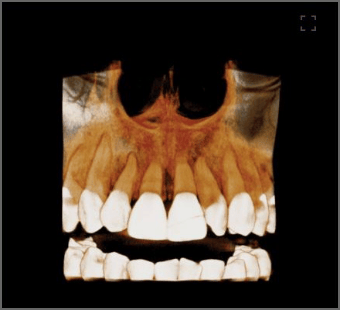

前額から顎下まで、歪の無い画像取得。FOV180×160

発展するデジタル広域解析に対応した撮影領域。

3D矯正解析、3D口腔内模型、3D顔貌それぞれのデータを融合した総合解析に対応するこれからのCTモデル。 精巧なそれぞれのデジタル診療情報を包括的に解析するための次世代診療に適した広域CT情報を提供します。

非合成の360度フルスキャン

データ合成無く、1回で360度フルスキャン N点(眉間)からGn点(顎)まで、わずか16秒でスキャン、広範囲を迅速かつ正確に診断します。